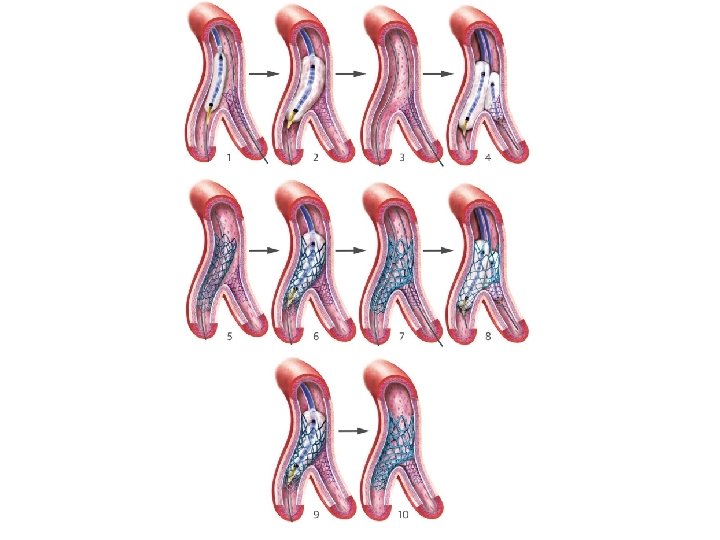

DK crush